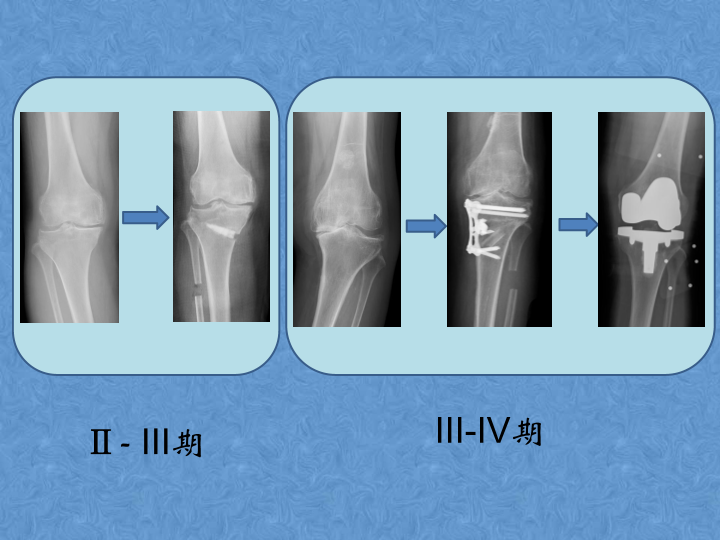

骨关节炎的阶梯治疗